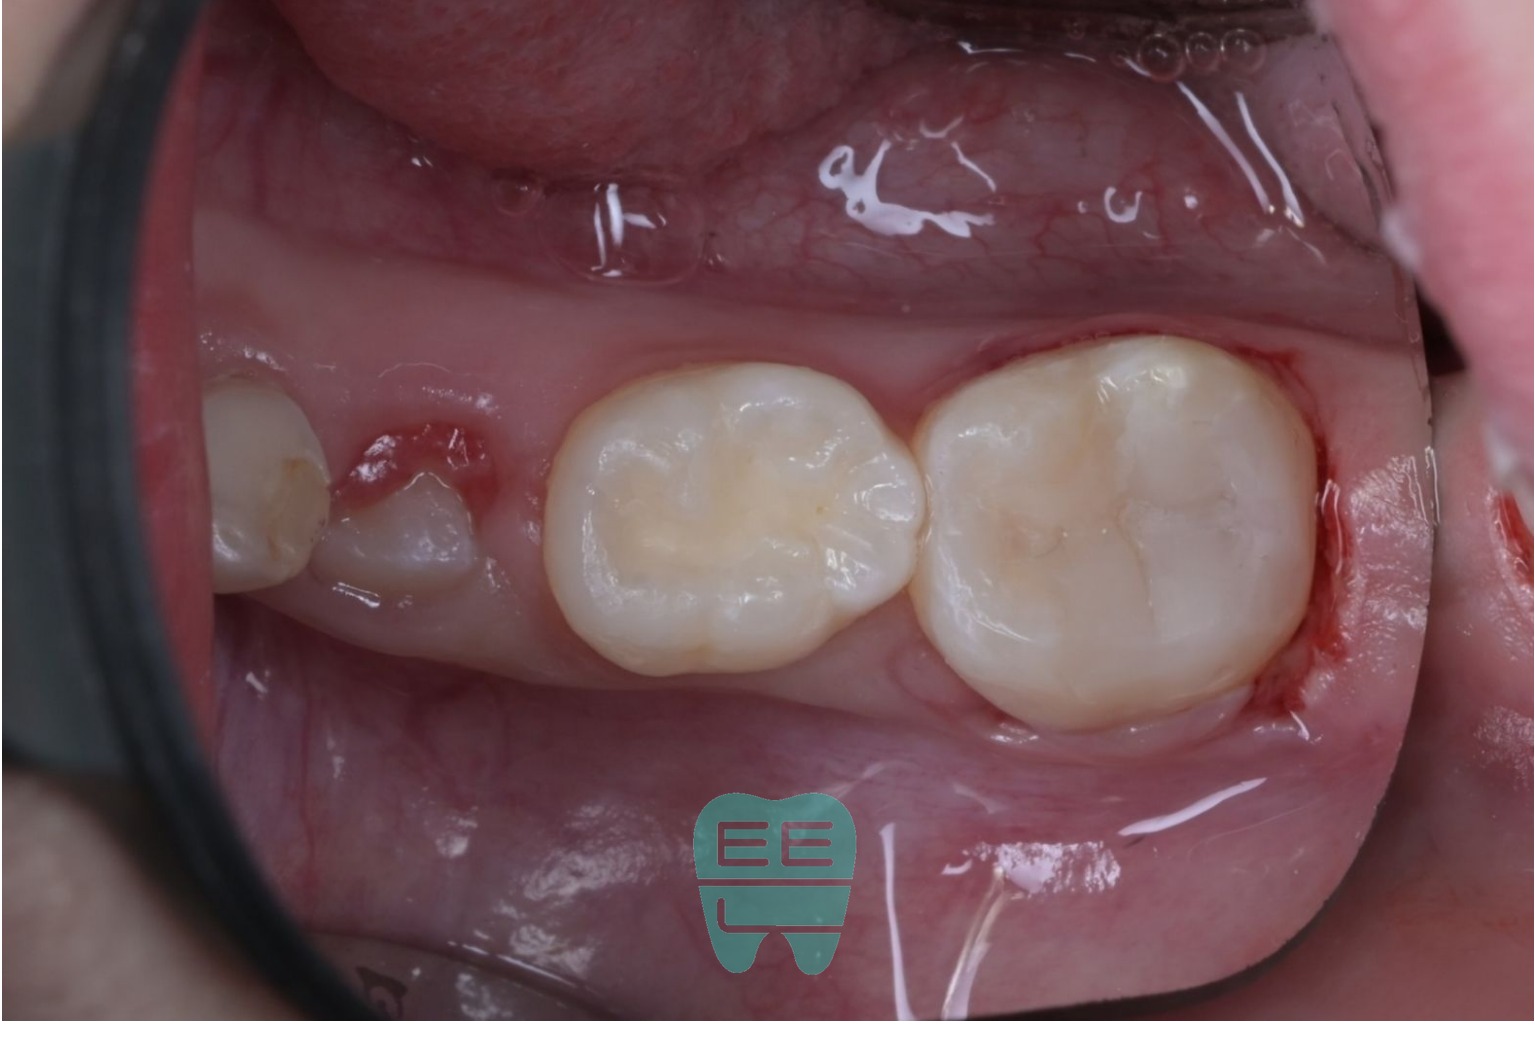

9. 레진 빌드업 완료

미세현미경 아래에서 복합레진을 층간 충전하여 자연 치아의 교합면 형태를 재현했습니다.

다른 각도에서 본 모습입니다. 입체적으로 적절한 외형이 회복된 것을 확인할 수 있습니다.

10. 치료 완료: 교합조정과 연마

교합조정과 연마를 마친 최종 모습입니다. 처음 들떠있던 레진과는 완전히 다릅니다. 주변 치아와 자연스럽게 어우러지는 형태와 색감, 그리고 정확한 교합이 확보되었습니다.